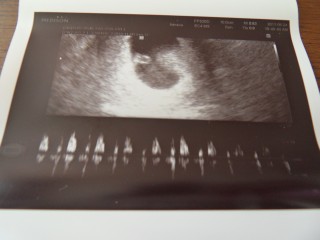

2週間前に行った時はただの黒くて丸い塊だったのに今日行ったら心拍も確認できるほど成長しててびっくり!!

6週1日目/GS=21.5㎜ 心拍を始めて確認できた日のエコーです。 7週目と思っていたら、6週目と言われました。ナゾ。次回、先生に聞いてみようと思います。